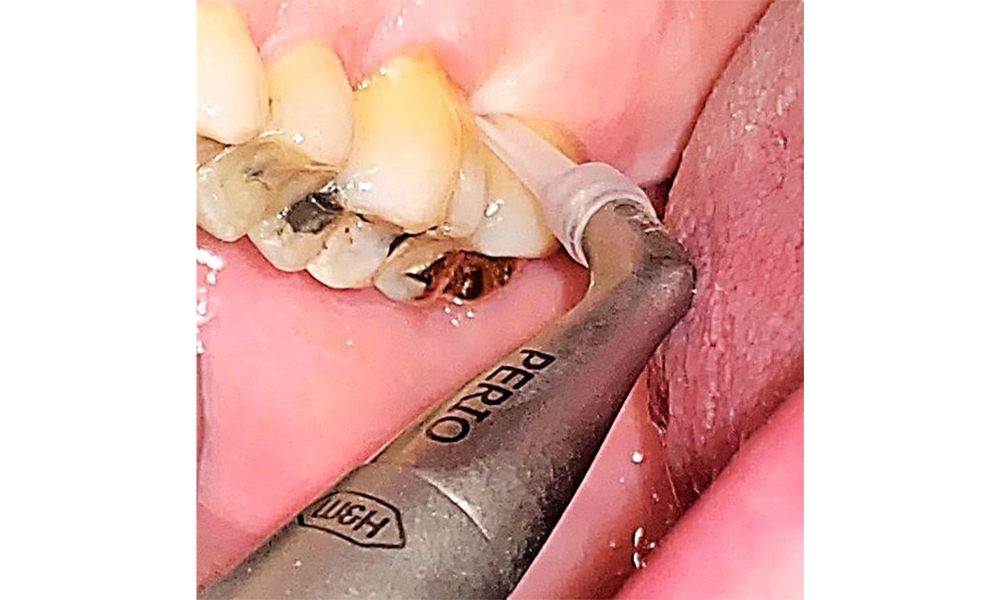

In der Instrumentierung sind bezüglich der Methodenwahl keine Einschränkungen gegeben. Aufgrund der parodontalen Vorerkrankung und dem hohen Rezidivrisikos ist die Vorbeugung einer Erkrankungsprogression durch die regelmäßige supra- und subgingivale Instrumentierung unerlässlich. Die Wahl der Instrumente zur mechanischen Biofilmentfernung ist aus allgemeingesundheitlicher Sicht nicht eingeschränkt und erfolgt bedarfsgerecht. Harte und mineralisierte Beläge wie Zahnstein und Konkremente sind mittels Handinstrumenten oder Schall/ Ultraschallscalern zu entfernen (Abb. 9) (8, 9).